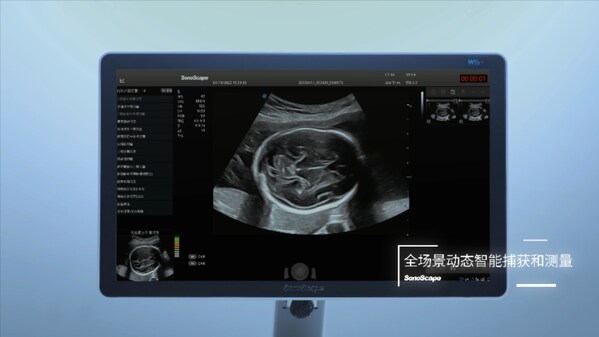

作為國內(nèi)首個獲批的產(chǎn)前超聲切面智能輔助識別與測量功能,鳳眼?S-Fetus®深度融合了超聲技術(shù)與人工智能,首個實現(xiàn)"全流程、全場景產(chǎn)篩智能化",讓開立超聲成為全球首個具備切面自動抓取、測量分析、超聲質(zhì)量控制的"整機智能",將積極推動產(chǎn)前超聲智能化轉(zhuǎn)型的進程。

鳳眼?S-Fetus®的問世帶來了前所未有的變革。作為國內(nèi)首個基于深度學(xué)習(xí)的產(chǎn)科超聲智能檢測技術(shù),鳳眼?S-Fetus®也是全球首款基于動態(tài)圖像對標準切面自動抓取的人工智能技術(shù),能夠?qū)Τ晥D像中的組織結(jié)構(gòu)進行實時檢測,自動抓取標準切面并進行自動測量,并實現(xiàn)了檢查過程中的實時質(zhì)控,顯著提高了產(chǎn)前超聲檢查的效率和準確性。

鳳眼?S-Fetus®支持精確的胎兒生物學(xué)測量,并自動發(fā)送至報告,使醫(yī)生的工作流更加順暢,有效節(jié)約了掃查時間,讓醫(yī)生更專注于患者的診斷與治療。"全流程、全場景產(chǎn)篩智能化"將有力為醫(yī)生的工作負荷做"減法",同時有助于提升基層醫(yī)生和年輕醫(yī)生獲取標準切面的能力,推動產(chǎn)前超聲技術(shù)的智能化、高效化發(fā)展,加速超聲行業(yè)的技術(shù)創(chuàng)新進程。